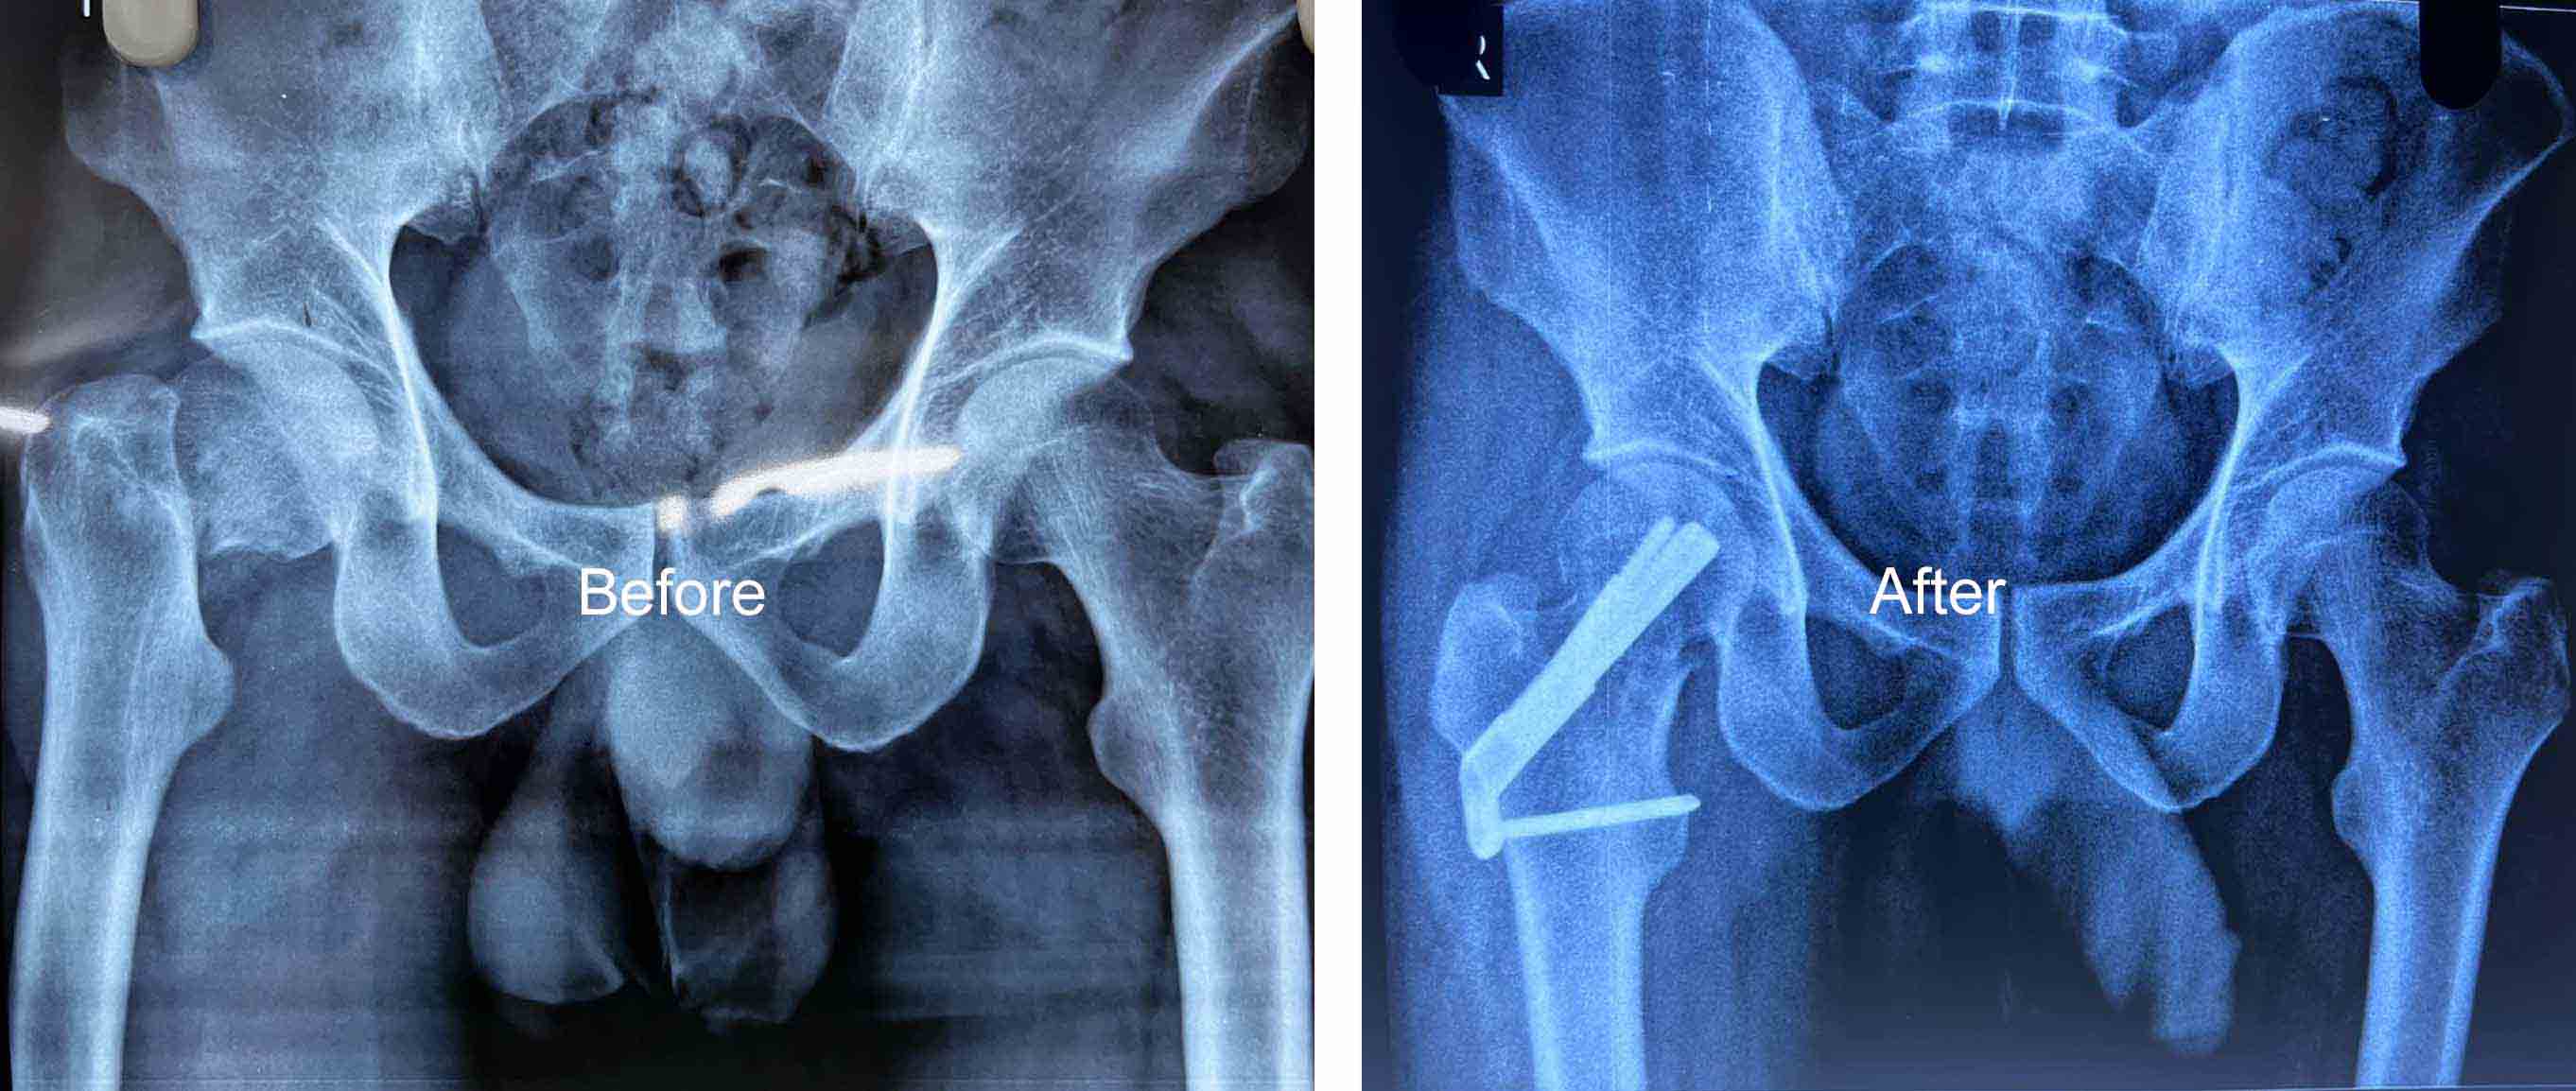

Dr Muhammed Riyadh is a distinguished medical professional in the field of orthopedics, has made significant contributions to the healthcare industry through a career marked by expertise, compassion, and unwavering dedication to patient well-being

Gallery